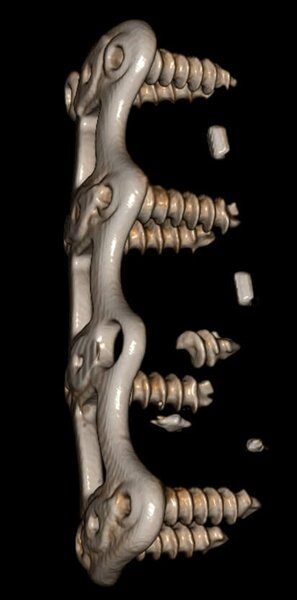

Newtom VGi evo ofrece una gama completa de FOV para la adquisición de volúmenes 3D nítidos y detallados, por lo que se adapta a cualquier necesidad clínica. La selección del campo de vista permite optimizar la región anatómica analizada garantizando un imaging de alta calidad con la mínima dosis posible.

El software NNT - Medical Suite ofrece una interfaz intuitiva y avanzada para efectuar, procesar y compartir exámenes 2D y 3D que mejora la gestión de las imágenes con instrumentos avanzados para la planificación de los tratamientos de implantología, endodoncia, periodoncia, cirugía maxilofacial y radiología. Un ecosistema integrado para una gestión diagnóstica de vanguardia.